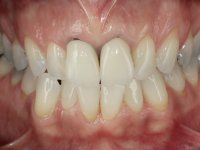

Foi proposta a substituição das duas coroas dos espigões falsos cotos fundidos após a realização de um branqueamento dentário. Equacionou-se também a possibilidade de refazer os tratamentos endodônticos, mas conclui-se que a remoção dos espigões falsos cotos teria um risco muito alto. Assim o plano de tratamento proposto resumiu-se à realização de um branqueamento dentário em ambulatório e à colocação de duas coroas com infraestrutura em Zr revestidas a cerâmica nos dentes 1,1 e 2.1.

O tratamento iniciou-se com a confeção de moldeiras transparentes em silicone para aplicação de peróxido de carbamida a 16%. Os espaçadores colocados na superfície vestibular foram cuidadosamente preparados em resina nos modelos de gesso. O tratamento foi feito aplicando o produto 2 horas por dia durante 8 dias. Após o branqueamento esperamos 4 semanas e iniciamos o tratamento prostodôntico. Foi realizada uma pré-impressão em silicone para confeção de uma ponte provisória com resina composta de polimerização dual. Em seguida iniciamos a remoção das coroas. Foi feito um corte vertical na zona média da coroa até encontrar a superfície do espigão falso coto fundido. No bordo incisal também foi realizado o mesmo corte. Em seguida com um luxador fino foi feita a separação das partes distais das coroas. Para a remoção das partes mesiais foi feito um corte na linha média abrangendo ambas as coroas. No final da remoção atraumática das coroas antigas os cotos foram re -preparados. Na re-preparação dos cotos a linha de acabamento foi colocada a nível intra-sulcular. Na mesma consulta foi feita a impressão definitiva. O afastamento gengival foi realizado com a técnica da pasta de caolino comprimida pela ponte provisória.  A impressão foi feita pela técnica de dupla mistura com dupla viscosidade com silicone de presa rápida. No laboratório foram confecionadas 2 coroas com infraestrutura em Zr sendo revestidas a cerâmica. No sentido de evitar aparência de coroas “muito altas” foi aumentado ligeiramente o diâmetro mesio-distal sobrepondo-se ligeiramente aos dentes adjacentes. A ponte provisória foi removida os cotos foram polidos e as coroas foram colocadas para verificação final. Confirmado o seu ajuste e aprovadas pela paciente foram cimentadas definitivamente com cimento de ionómero de vidro reforçado com resina.